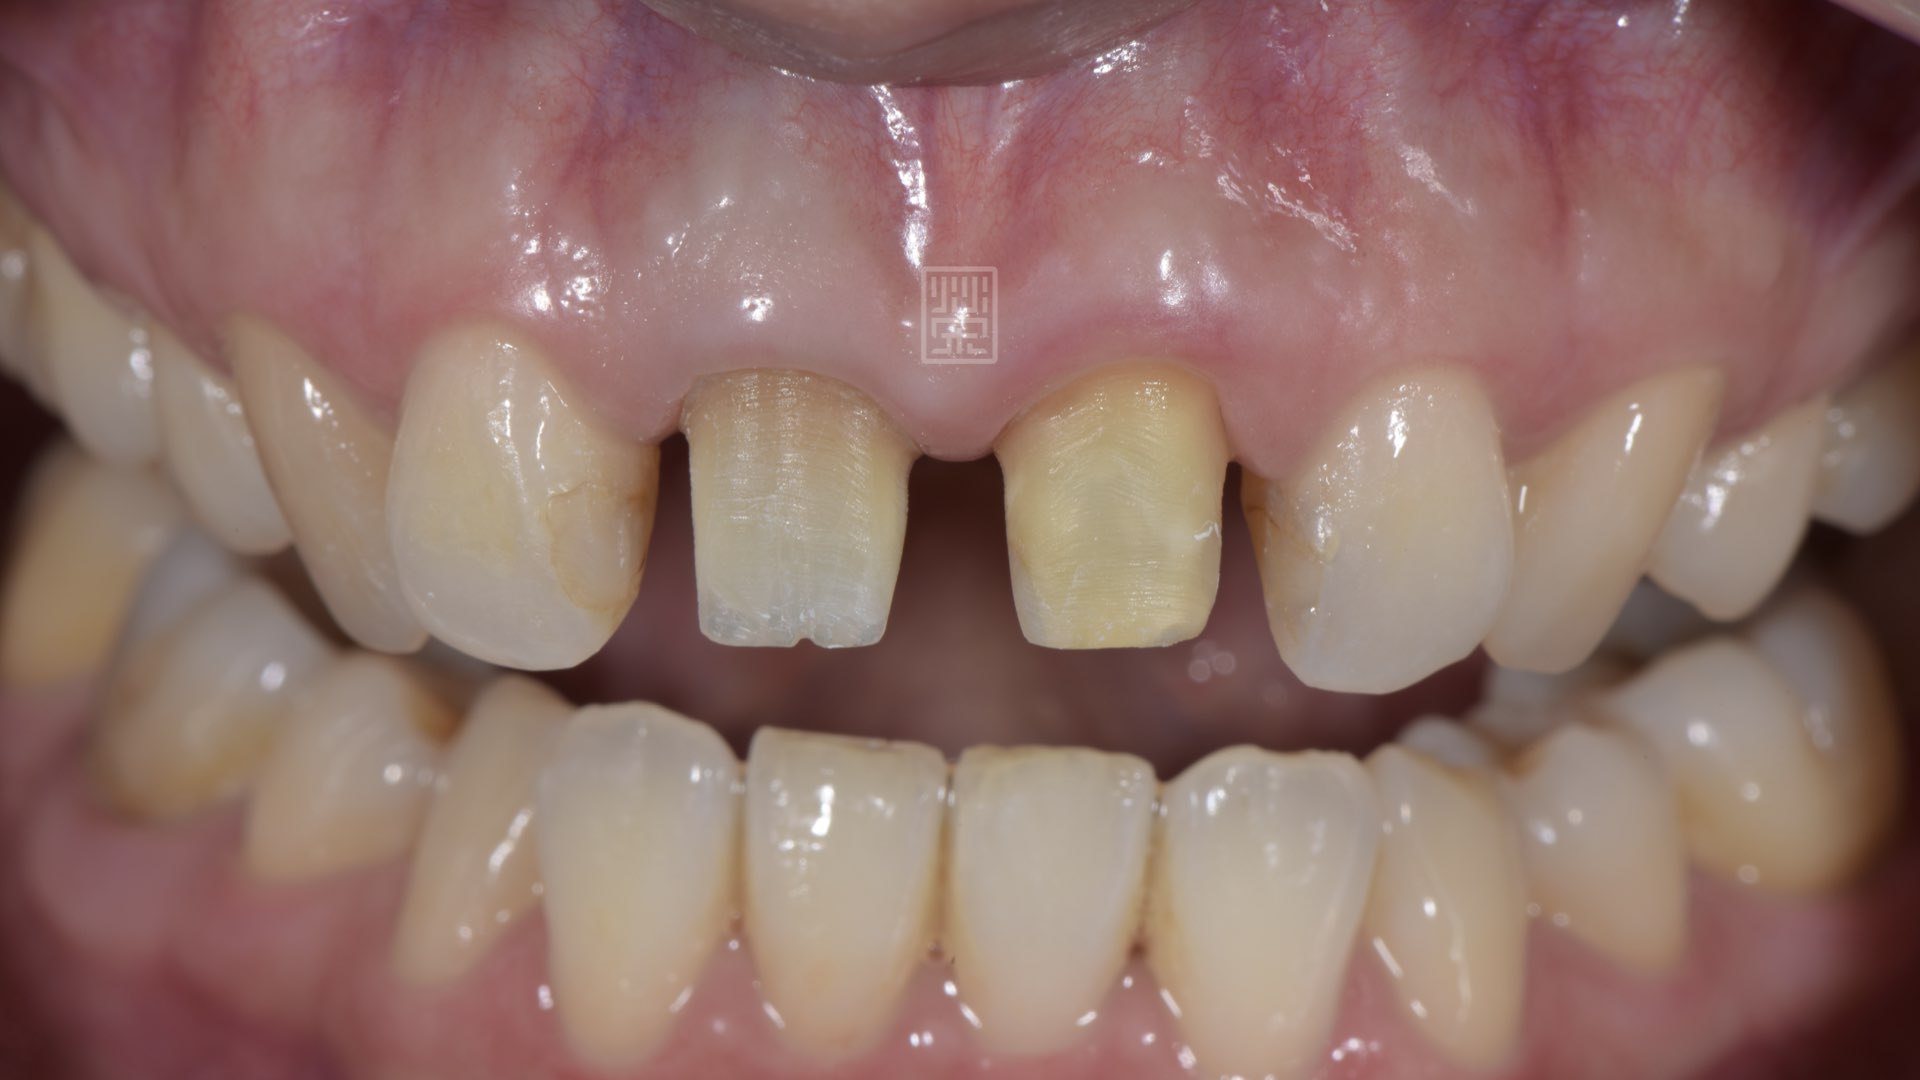

全瓷冠變色,牙齦萎縮

榮醫師診察後,主要是全瓷冠破裂,造成顏色與自然牙不同,但因為全瓷冠邊緣不密貼,長期造成牙齦發炎,所以牙齦有局部萎縮。